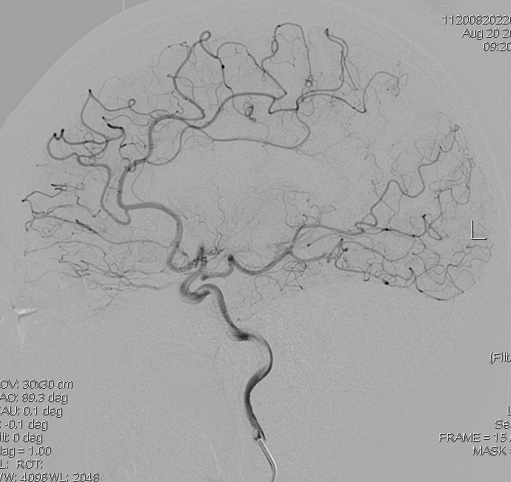

DSA显示右侧颈内动脉末端闭塞:

但是左侧是大脑中动脉闭塞:

所以,第一考虑不是烟雾病。

做右侧颞浅动脉-大脑中动脉搭桥+硬膜翻转颞肌贴敷术,手术过程没什么,受体血管约1mm。